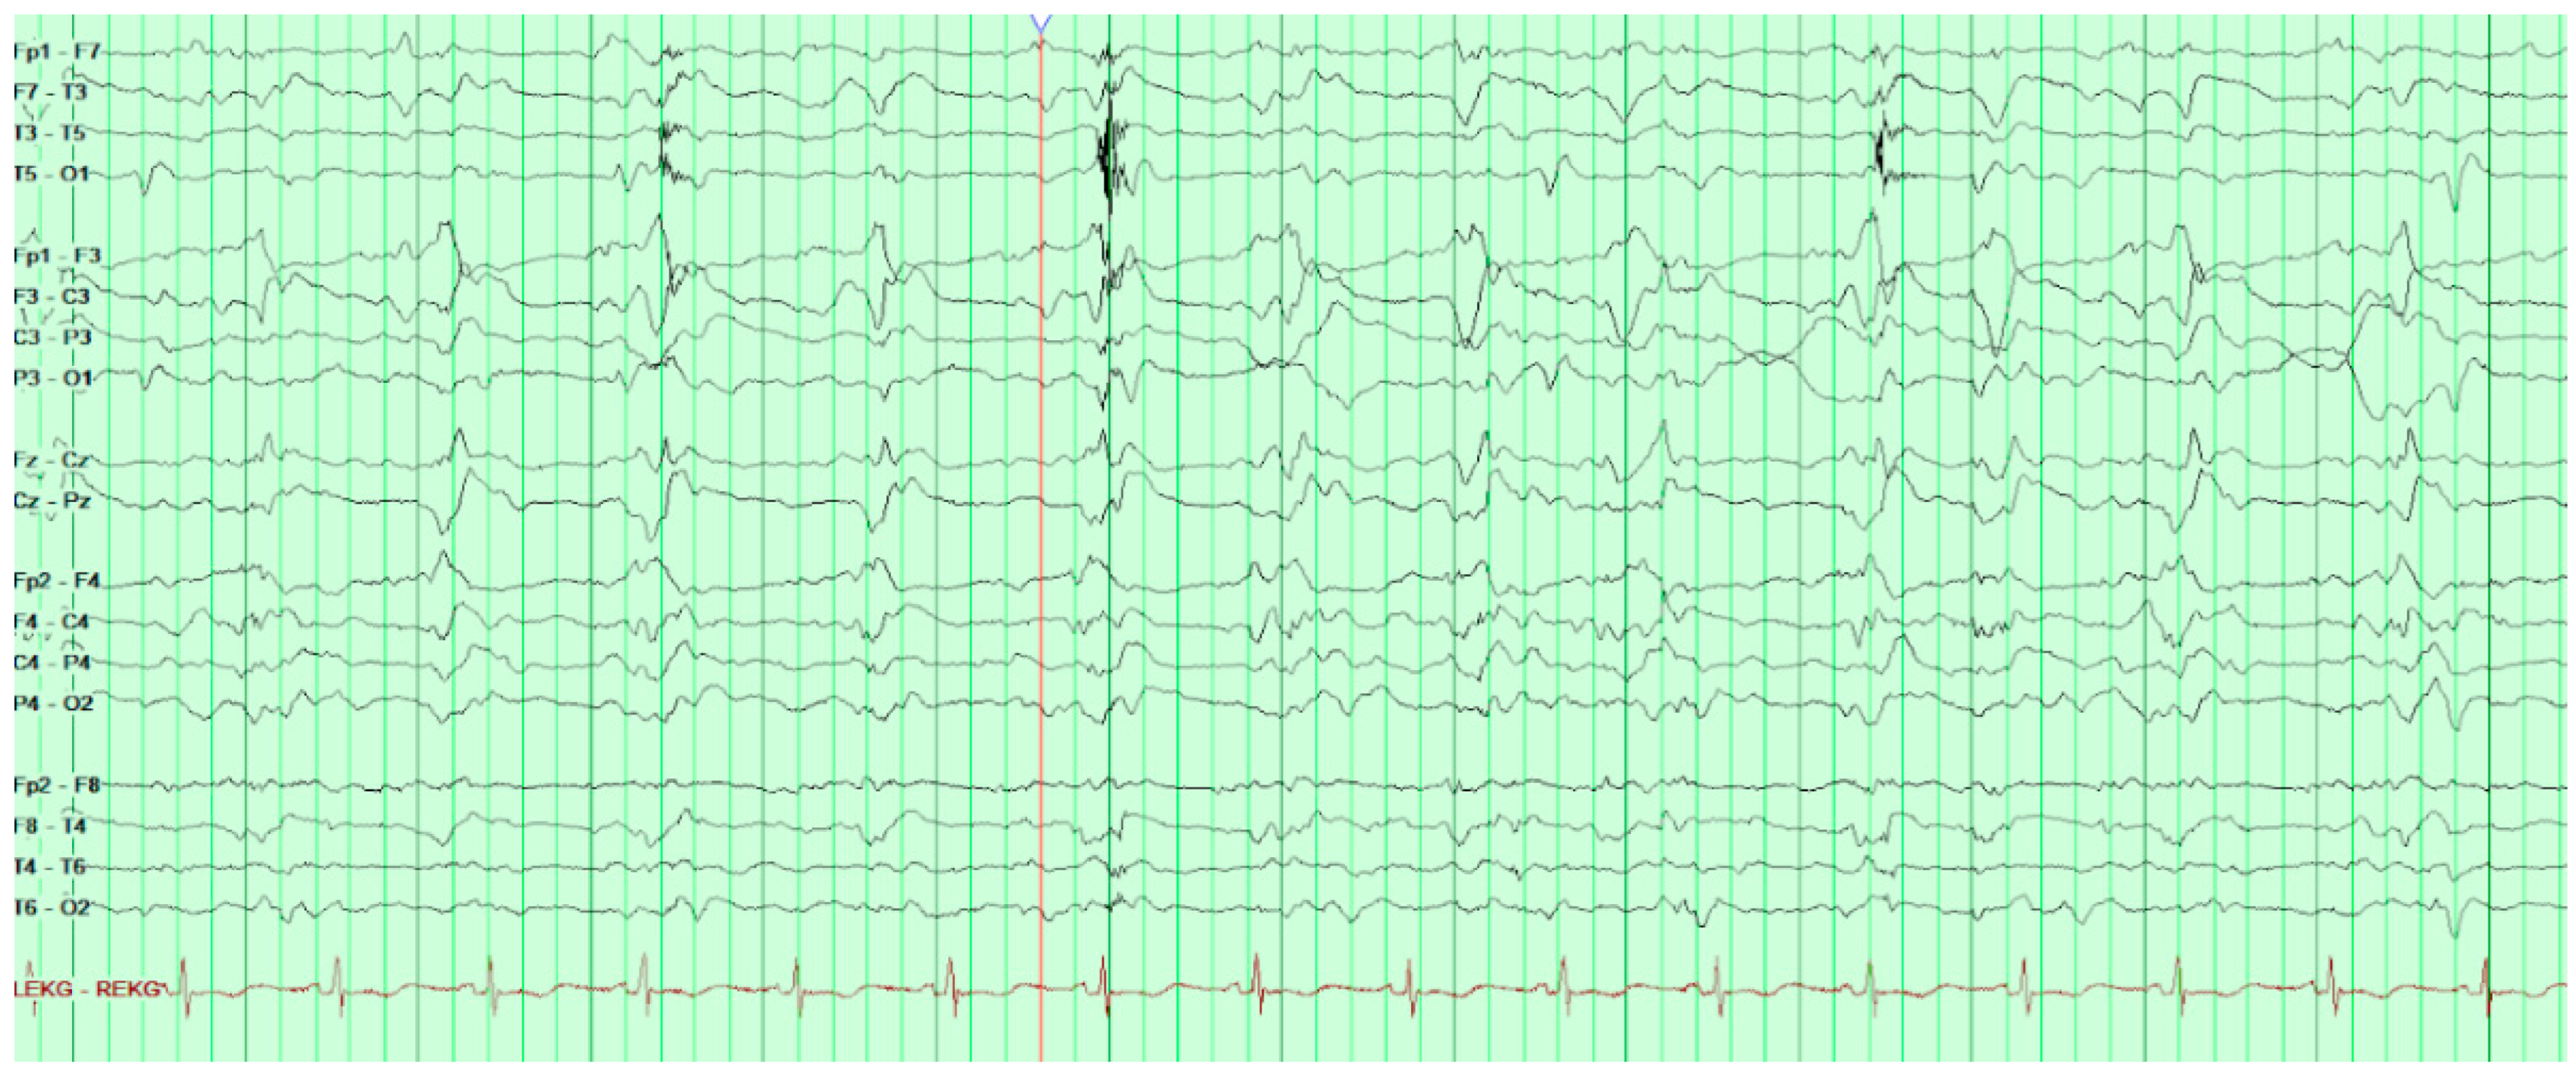

On HD80, after several days of increasing somnolence and ammonia levels rising above 250 µ/dL, the patient was started on hemodialysis and soon after his first run of dialysis, he was found to have a positive oculocephalic reflex “doll’s eyes test” and thus a stroke code was called. He was examined by neurology and was found to have minimal responses to sternal rub. His eyes were conjugate with pupils 8 mm and equal and reactive to light. Oculocephalics, corneal, and gag reflexes were intact at the time. Roving eye movements were not observed though the patient’s eyes had deviated to the right. The patient had no abnormal movements, no response to painful stimuli, and was found to be diffusely hyporeflexic yet symmetric in biceps, brachioradialis, patellar, and achilles. Head CT without contrast was obtained and found to be unremarkable. Consideration was given to stroke, but this was felt far less likely given the normal head CT. Concern for seizure was also raised although no acute treatment was given at the time; however, EEG was later ordered and revealed frequent bilateral occipital epileptiform activity (

Figure 3).

During EEG monitoring, the patient had a total of 19 recorded seizures. Three of the seizures were prolonged (lasting 15–30 min each) and had clinical signs of head jerking and facial twitching. All seizures showed bilateral occipital onset with rhythmic and repetitive sharps which evolved in both frequency and amplitude with right occipital predominance. There were 16 subclinical seizures recorded with bilateral occipital activities, and also with right occipital predominance. These findings were consistent with status epilepticus and the patient was loaded with IV levetiracetam and then started on a midazolam drip with burst suppression. Overnight the patient proceeded into non-convulsive status epilepticus (NCSE) and required IV lacosamide. He was on 10 mg/hr midazolam which was then weaned abruptly the following day. That night the patient emerged into convulsive status epilepticus and was re-bolused with midazolam, which was then increased serially up to 50 mg/hr with no effect over the next two hours. He was then loaded with fosphenytoin which for several hours resulted in dissipation of convulsive activity and <2.5 Hz Bi-PLEDs (bilateral-type periodic epileptiform discharges). Two hours later, the patient returned to NCSE with 1 Hz Bi-PLED activity noted. Ketamine was loaded at this point and all seizure activity stopped. EEG was noted flatlining and a head CT was obtained revealing profound edema (